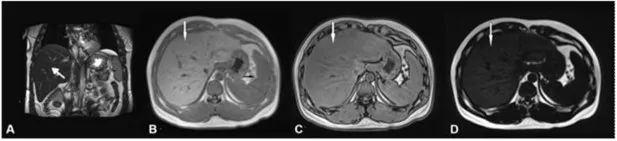

脂肪肝是一种常见的肝脏病理改变,即肝细胞内积累了过多的脂肪,因此在反相位图像上,脂肪浸润的信号比同相位图像的信号强度明显下降(图2),其诊断敏感性超过常规MRI和CT。此外,有研究对多回波Dixon技术测得的PDFF与组织病理学脂肪含量进行了相关性分析,证实了其在脂肪肝分级诊断中的价值。欧洲肝脏研究协会已将PDFF作为一种可诊断肝脏脂肪变性的无创性参考指标纳入非酒精性脂肪性肝病(NAFLD)的指南当中。基于多回波Dixon技术得到的PDFF可重复性好,可实现脂肪的精确定量,适合对病情长期随访,但目前尚缺乏统一的标准值或范围来界定脂肪肝程度及确定临床治疗终点。

图2:一名脂肪肝患者的CSI。a)冠状位T2加权成像显示肝脏体积轻度增大,相比脾脏呈低信号;b)肝实质在同相位上呈高信号;c)肝实质在反相位上呈低信号;d)由于脂含量增高,脂图上呈稍高信号。